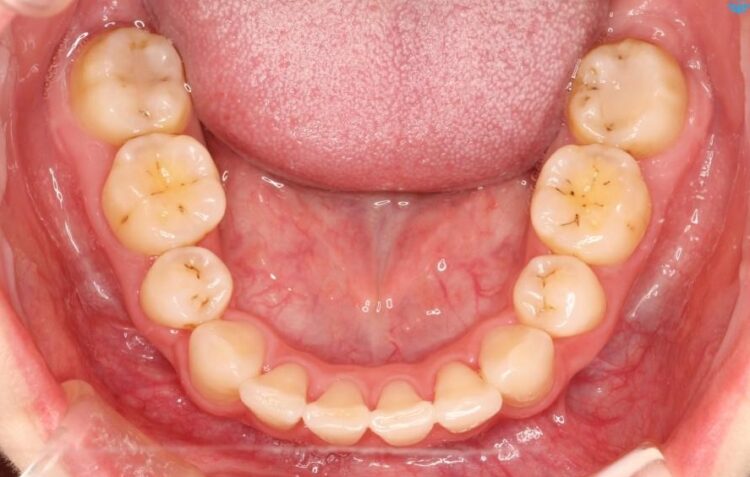

【20代女性】出っ歯の矯正 治療例

口元が出ていることを気にされて来院されました。

治療費の安い矯正治療を希望されていたため、メタルのワイヤー装置にて治療する計画にしました。また、歯みがきが苦手だったため、矯正治療をする前に徹底的にブラッシング指導を行いました。

出ている歯を引っ込めるためのスペースを作るため、上下左右の小臼歯を抜歯し、ワイヤー矯正を行いました。治療後は、口元がスッキリとしたことで患者様にも喜んでいいただきました。